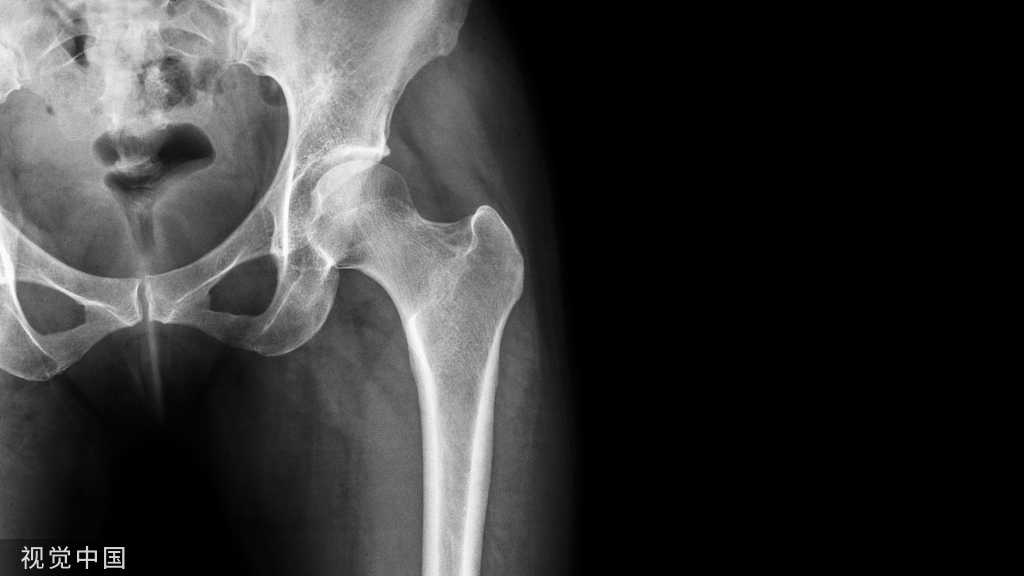

▶▶下肢力线

- 也称作下肢机械轴线。

- 站立前后位股骨头中心与踝关节中心的连线。

- 通过膝关节中心。

- 膝内翻时,位于膝关节中心内侧;外翻时,位于膝关节中心外侧。

▶▶中心点确立方法

1.由于股骨头是一个相对比较规则的圆形,使用Mose圈或圆规很容易确定股骨头中心。